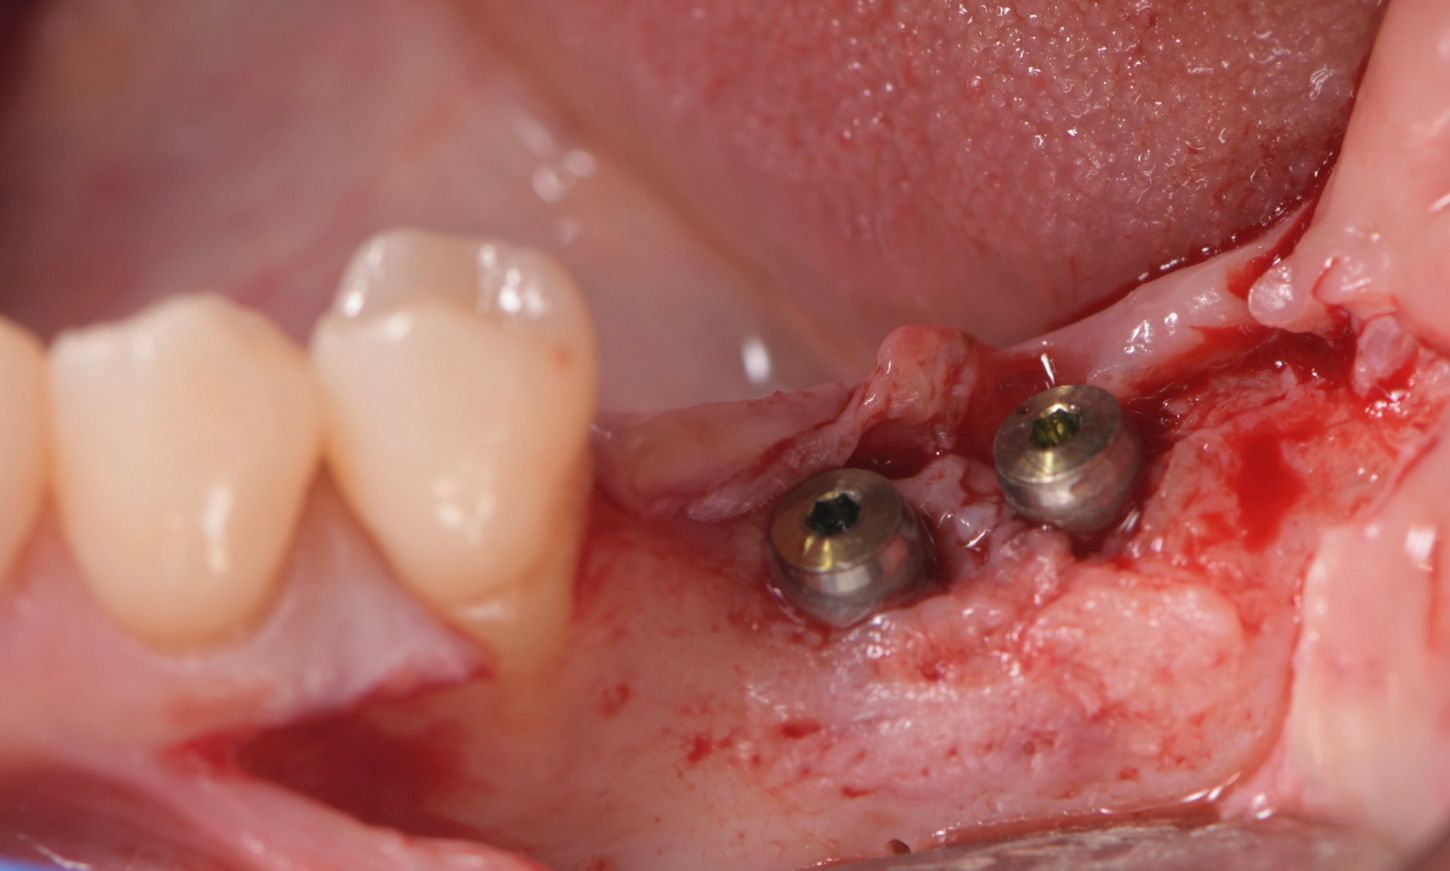

In 2021, six months after the initial surgery, a full-thickness flap was elevated, revealing that the implants were surrounded by bone (Figs. 14,15). Healing abutments were then inserted, and interrupted sutures were inserted using 6/0 prolene (Fig. 16). The healing abutments play an essential role in facilitating proper healing of the gingival tissue around the implant, shaping the tissue for an optimal fit of the final prosthesis, and protecting the implant from contaminants.